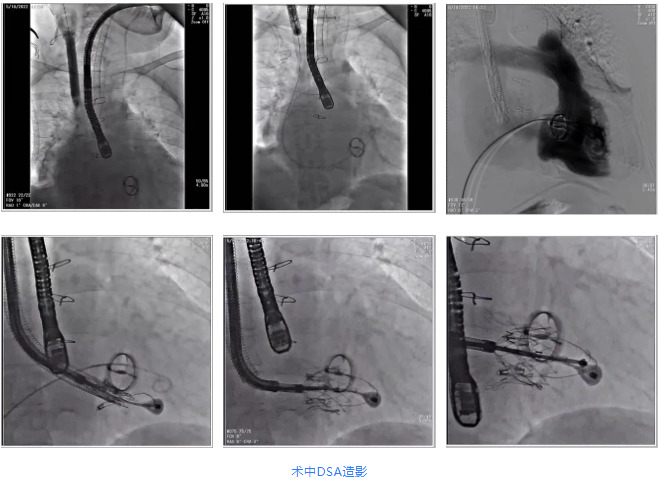

根據(jù)術(shù)前評(píng)估結(jié)果,郭應(yīng)強(qiáng)教授團(tuán)隊(duì)為患者量身定制了手術(shù)策略,決定使用LuX-Valve Plus經(jīng)血管三尖瓣置換系統(tǒng)開展手術(shù)治療。手術(shù)在全麻下進(jìn)行,采用經(jīng)右側(cè)頸靜脈入路,在經(jīng)食道超聲和DSA的指引下調(diào)整輸送器角度以達(dá)到正確位置,勾住前瓣后逐步釋放盤片,盤片打開后順利扎針,最終完成瓣膜植入,輸送器撤出。術(shù)后超聲提示人工三尖瓣同軸性良好,瓣架固定牢靠,無反流和瓣周漏,術(shù)后三尖瓣平均跨瓣壓差為1 mmHg。